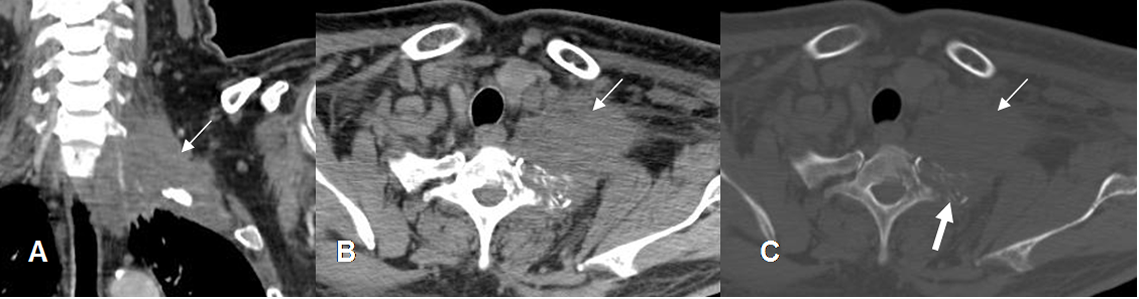

Fig 11. Neoplasia de pulmón.

A: TAC reconstrucción coronal, B: TAC axial en ventana de tejido y C en ventana ósea. Tumor pulmonar con extensión al espacio interescalénico. (Flechas delgadas). Hay destrucción ósea en la apófisis transversa vertebral y el origen de la costilla. (Flechas gruesas).